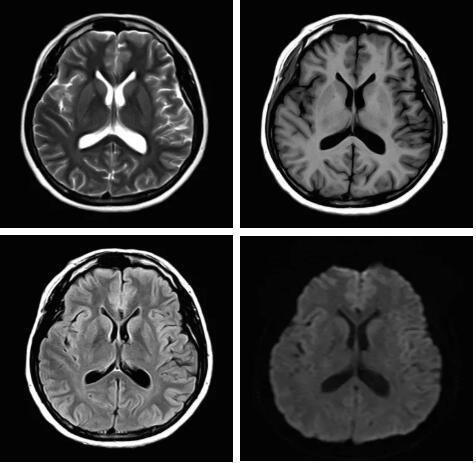

眾所周知,磁共振成像最核心的三個(gè)部分:磁體、梯度、射頻,此三部分為磁共振成像之魂,直接決定著磁共振成像的圖像質(zhì)量--圖像信噪比。各個(gè)廠家在磁共振成像提升圖像信噪比的道路上不斷探索和創(chuàng)新,致力于信噪比的提升,各個(gè)廠家側(cè)重點(diǎn)不同,在各自領(lǐng)域各有所長,在本世紀(jì)第二個(gè)十年,各個(gè)廠家都在做不同的嘗試和改進(jìn),例如:A廠家的“太空艙”技術(shù),旨在解決射頻發(fā)射和射頻接收的實(shí)時(shí)互補(bǔ)……;B廠家的ADC前置所謂的“全數(shù)字”技術(shù),旨在解決信號(hào)模數(shù)轉(zhuǎn)換的時(shí)間早晚……;C廠家的“光纖”技術(shù),旨在解決信號(hào)傳輸路徑的信號(hào)損失……;各家都在一定程度上解決了信號(hào)的損失,信噪比在一定程度上有所提升,但是并未從根本上解決信噪比大幅度提升。

3.Pure射頻成像鏈

從成像源頭的磁體采用鍍膜新磁體高密度薄層鍍膜貼合技術(shù),獲得更好的磁場(chǎng)均勻度,奠定磁共振成像基礎(chǔ);采用3D RSCE微雕梯度精準(zhǔn)控制頻率和相位,輸出理想波形,實(shí)現(xiàn)渦流的“0”殘余,還原最真實(shí)的圖像信息;射頻接收端通過計(jì)算機(jī)人工智能對(duì)信號(hào)抗干擾處理,把信號(hào)放大并去除梯度、磁場(chǎng)等對(duì)信號(hào)干擾,再經(jīng)過二次人工智能信號(hào)識(shí)別,去除噪聲污染獲得純凈的信號(hào);通過Pure射頻成像鏈的優(yōu)化和改進(jìn)使信噪比提升40%,這是磁共振領(lǐng)域革命性的顛覆和改變。